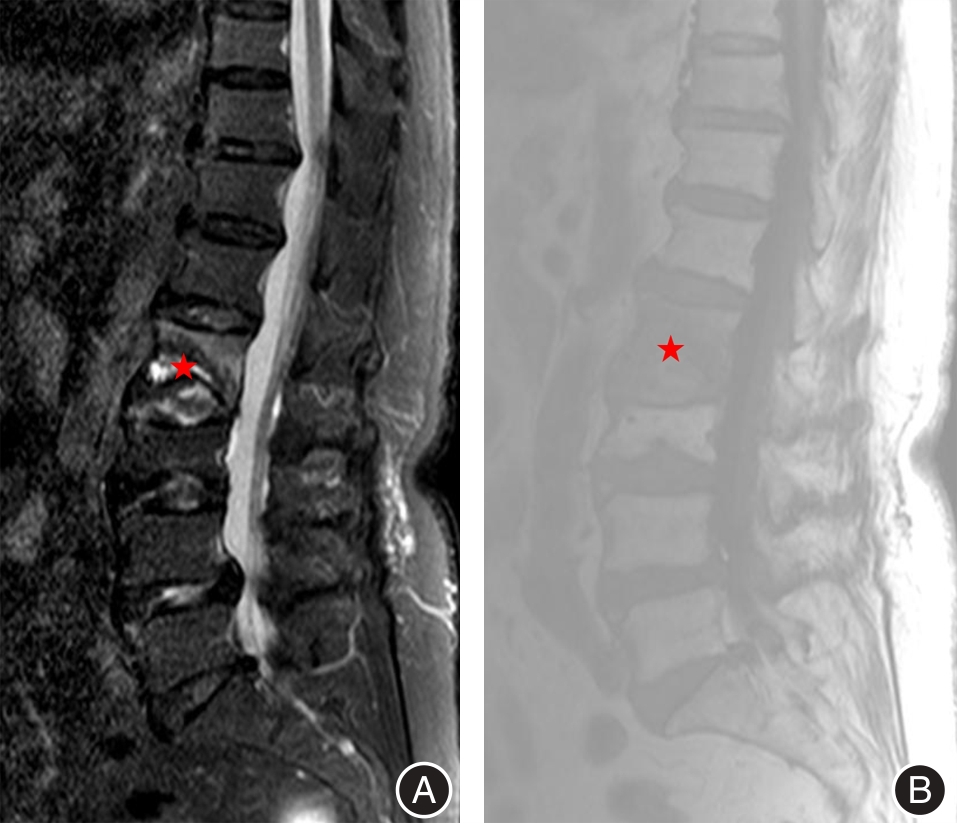

目的 探究经皮椎体成形术(PVP)治疗骨质疏松性椎体骨折(OVF)后早期残余腰背痛的影响因素,为临床干预提供依据。 方法 回顾性分析2020年7月至2025年6月接受PVP治疗的1 120例OVF患者,筛选出61例术后早期(术后2 d至1个月)残余腰背痛患者(术后VAS评分> 3分,观察组),采用1∶1匹配原则(按年龄± 5岁、术前骨密度± 0.5SD)选取61例对照,进行单因素及logistic回归分析。 结果 单因素分析显示,术前胸腰筋膜损伤(TFI)、患椎MRI液化信号、责任椎体数(≥ 2个)及骨水泥分布不佳在两组间差异有统计学意义(P < 0.05);多因素回归表明,上述因素为独立危险因素(OR值分别为5.378、6.111、3.245、2.890,P < 0.05)。模型AUC为0.929,提示预测效能良好。 结论 术前TFI、患椎MRI液化信号、多责任椎体及骨水泥分布不佳可能增加PVP术后早期残余腰背痛风险。

Objective To investigate the factors influencing the persistence of residual low back pain following percutaneous vertebroplasty (PVP) in patients with osteoporotic vertebral fractures (OVF), in order to provide a scientific basis for clinical intervention strategies. Methods A retrospective analysis was conducted on data from 1 120 patients diagnosed with OVF who received PVP treatment between July 2020 and June 2025. Among them, 61 patients who experienced residual low back pain in the early postoperative period (defined as 2 days to 1 month after surgery) with a postoperative visual analog scale (VAS) score greater than 3 points were selected as the observation group. An additional 61 control subjects were matched to the observation group at a 1∶1 ratio based on age (± 5 years), gender, and preoperative bone mineral density (± 0.5 standard deviation). Univariate and logistic regression analyses were subsequently performed to evaluate potential influencing factors. Results Univariate analysis revealed statistically significant differences between the two groups with respect to preoperative thoracolumbar fascia injury (TFI), MRI-detected liquefaction signals in the affected vertebrae, the number of involved vertebrae (≥ 2), and suboptimal bone cement distribution (P < 0.05). Multivariate regression analysis confirmed that these factors were independent risk factors, with corresponding odds ratios (ORs) of 5.378, 6.111, 3.245, and 2.890 (all P < 0.05). The area under the curve (AUC) of the predictive model was 0.929, indicating a high level of predictive accuracy. Conclusion Preoperative TFI, MRI-demonstrated liquefaction signals in the affected vertebrae, the presence of multiple responsible vertebrae, and suboptimal bone cement distribution may contribute to an increased risk of early residual low back pain following PVP.